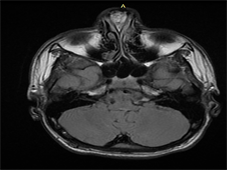

We ordered a CT scan of the nose and paranasal sinuses [Figure 1] which showed a swelling on the dorsum of the nose with splaying of the nasal bones. Also a MRI with contrast [Figure 2] was done which showed mixed signal intensity mass lesion which approximately measures 2.69 × 1.50 cms in the anterior nasal cavity within the anterior septum, associated with sinus tract extending superiorly to the foramen caecum with no intracranial extension.

Figure 2. Magnetic resonance imaging of brain with gadolinium contrast showed mixed signal intensity mass lesion which approximately measures 2.69 × 1.50 cms in the anterior nasal cavity within the anterior septum, associated with sinus tract extending superiorly to the foramen caecum with no intracranial extension.